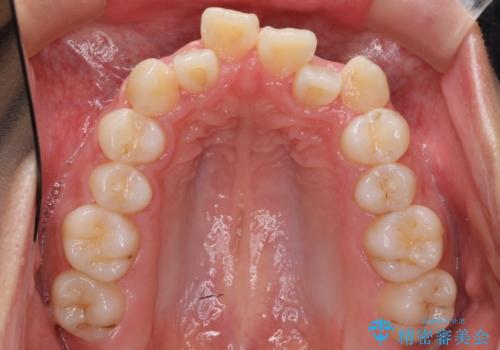

リファインメントもなく、1回で治療が終了しました。大変うまくいったケースです。

主治医としては、前歯の並びをもう少しこだわりたかったのですが、満足度が高く、リファインメントは希望されませんでした。

抜歯をしていないので口元は変わっていません。

八重歯も重症でなければインビザラインでも並びを歯を抜かずに整えることができます。